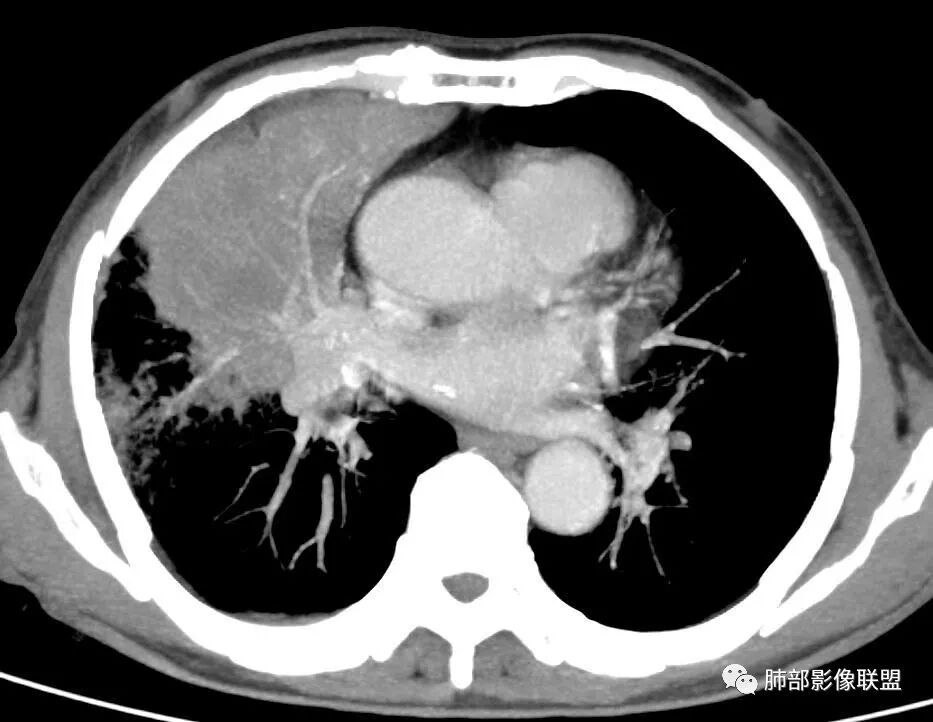

晨读病例,老年男性,乏力,纳差,近来发热,右肺上叶团片状阴影,内见空洞,空洞内壁不光滑,见短液平,增强病灶壁可见不均匀强化,似有边界不清晰的坏死,病灶周围可见片状模糊阴影,考虑恶性病变,鳞癌或腺癌伴感染。

老年男性,肺气肿背景,右肺较大分叶状肿块,密度不均,内坏死空洞形成,坏死区边界不规则,周围多发斑片蜂窝状、网格状高密度影,考虑鳞癌合并感染

右肺上叶及中叶不规则肿块伴周围模糊影,其内小叶间质结节样改变,肿块不均匀强化,坏死及空洞,坏死边界不清,血管显示尚可,考虑腺癌,鉴别淋巴瘤

老年男性,有咳嗽发热。右肺中上叶团状软组织肿块,周围磨玻璃渗出改变,病灶内密度不均,可见低密度坏死及空洞影,空洞内壁凹凸不平,近肺门侧可见明显大面积坏死。近端支气管堵塞不明显。考虑恶性肿瘤伴感染,腺癌?鉴别鳞癌,感染性病变。

右肺上叶团片状阴影,内见空洞,空洞内壁不光滑,偏心,,增强不均匀强化,内有边界不清晰的坏死,病灶周围可见片状模糊阴影,右下肺也有磨玻璃病灶,Crp高,腺癌

70岁男性,发烧病史,右肺巨大肿块,边缘分叶,内部空洞,洞内见附壁结节,局部支气管阻塞,肿块周围见大片阻塞性炎症;实验室检查,炎性指标增高;考虑恶性肿瘤伴阻塞性肺炎,鳞癌可能。

老年男性,乏力,纳差,发热。右肺上叶团片状阴影,密度不均,可见低密度坏死,坏死边界不清,可见空洞形成,见短液平;增强病灶呈不均匀强化,其内血管边缘模糊毛糙;病灶周围可见斑片状渗出病灶,支气管未见明确阻塞。综上考虑肺癌伴感染,鳞癌可能。

老年男性,纳差和发热,炎症指标明显。右肺磨玻璃影伴有肿块,肿块呈膨胀性生长,内部没有气管影。首先考虑感染,并有肿瘤的表现。考虑鳞癌合并感染

右肺上叶实变,密度不均,内可见小气液平,周磨玻璃影,斜裂稍内凹,右下肺可见斑片影,强化可见血管走行自如,右侧胸腔少量积液,考虑感染性病变,努卡?放线菌?

老年男性,肺气肿背景,右肺上叶及中叶大范围实变影,边界不清,支气管通畅,其内见边缘膨隆软组织块影伴不规则坏死、空洞,增强扫描不均匀强化,洞壁显示不清,血管稍变细,实变影内另见多发囊样影,右肺下叶小片状影,病灶跨叶,炎性指标增高,感染应该有的,不除外合并恶性肿瘤(鳞癌?腺癌?)

男,70,反复乏力、纳差20天,发热1天。胸部CT:肺气肿背景,右肺上叶中叶大团片影,实变十磨玻璃渗出。增强实性斑片影内密度不均,可见多发低密度坏死及不规则空洞影,空洞内壁尚光滑,血管边缘模糊。支气管管壁增厚,管腔通畅。右下叶可见小片渗出影。考虑支气管肺炎进展?病原考虑能形成肉芽肿、坏死空洞的微生物,TB?奴卡?鉴别鳞癌。

老年男性,乏力纳差,进食量明显下降,发热,后期少许黄脓痰,无咯血。无胸痛。未提口腔卫生情况,发热时间段不明确,肺气肿背景,气管内痰拴还是其他?觉得是外朝内进展病灶,右肺多叶段病灶,支气管通畅,支气管壁弥漫增厚,实变病灶内有坏死,坏死边界比较清晰,血管破坏不明显,周围散在磨玻璃,边界模糊,无树芽,实变内可疑小钙化,右侧胸水,肺门纵隔淋巴结无明显肿大。病史不太支持化脓菌感染,真菌里隐球强化不太支持,结核需要排除,厌氧菌感染带排,冠状位矢状位病灶觉得类圆形,临床肿瘤也是不能轻易排除的